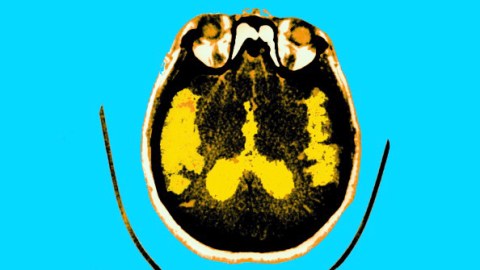

Image courtesy of BSIP / Getty Contributor

Scan Of The Brain Of A Patient Affected By Alzheimer’s Disease Axial Section. Median Portion Of Dilated Third Ventricle. Symmetrical And Rounded Dilation Of Intersections. Sylvian Fissure Is Quite Enlarged.